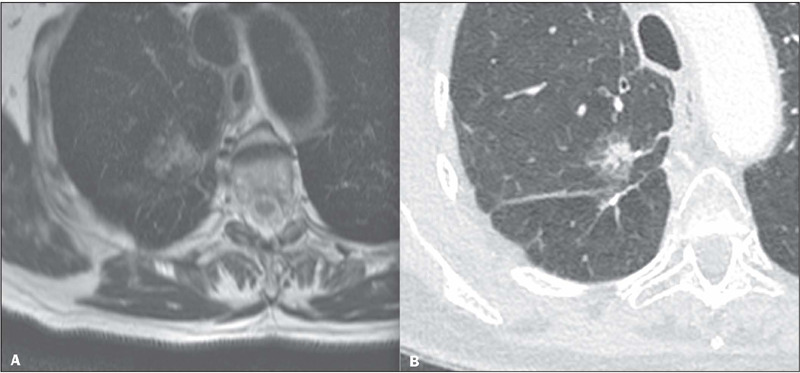

Results: Most of the examinations (31 of the LL T1 relaxometry sequences and 36 of the HR T2 sequences) were of adequate diagnostic quality. Nondiagnostic examinations were considered so mainly because of limited coverage of the sequences. Of the FLLs studied, 19 were malignant, 17 were benign, and three were excluded from the accuracy analysis because there was no definitive diagnosis. Although LL T1 relaxometry could not distinguish between benign and malignant lesions, the signal intensity at its first inversion time (160 ms) differed between the two groups. The HR T2 sequence was considered the best sequence for assessing specific morphological characteristics, especially pseudocavities and pleural tags. We found that MRI showed better accuracy than did computed tomography (86% vs. 74%).

Conclusion: Both MRI sequences are feasible for the evaluation of FLLs. Images at 160 ms of the LL T1 relaxometry sequence helped distinguish between benign and malignant lesions, and the HR T2 sequence was considered the best sequence for evaluating specific morphological characteristics.